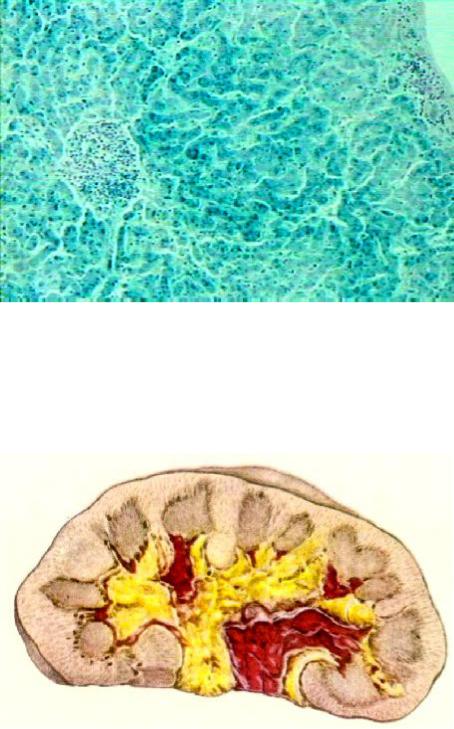

В печени под капсулой отмечают одиночные мелкоочаговые кровоизлия- ния, признаки застойного полнокровия. В гепатоцитах убывает количество гликогена, возрастает количество нейтрального жира, нарастают белковая зернистая дистрофия и гемосидероз (рис. 84). Количество звездчатых ретику- лоэндотелиоцитов уменьшается, фагоцитарная способность их подавлена.

Рис. 84. Микропрепа- рат печени при гема-

тологической форме ОЛБ: в гепатоцитах

зернистая дистро- фия и отложения зе-

рен гемосидерина (окраска по Перлсу,

× 200)